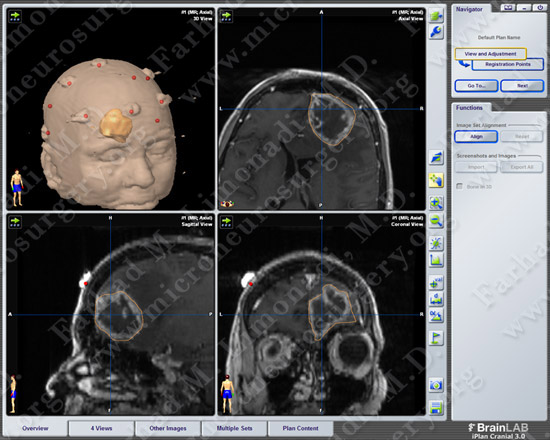

Computer Navigation

Computer navigation shows stereotactic mapping and approach to the tumor.